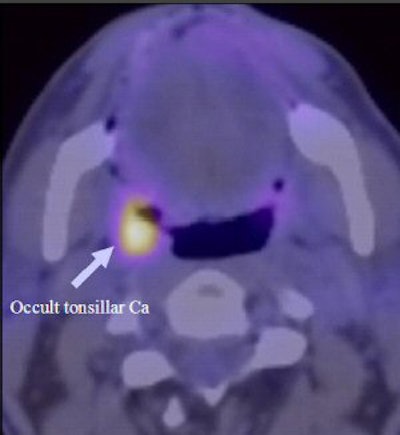

| FDG-PET/CT clinical images show a tonsillar cancer (above), a positive neck node, and lateral node (below). Images courtesy of Paul Strickland Scanner Centre. |

According to the study results, FDG-PET/CT identified the primary site of cancer in 30 of 78 patients. The findings were confirmed histologically, with 14 of the 30 sites at the base of the tongue and 14 primary cancers detected at the pharyngeal palatine tonsils. Sixteen of the 78 patients had "suspicious" FDG uptake in the PET/CT scan, which could not be confirmed subsequently at biopsy. Of those, 12 were at the pharyngeal palatine tonsils, with the other four at the base of the tongue.

FDG-PET/CT also was able to detect unexpected sites of disease in six patients, who had uptake in contralateral neck nodes. In one patient, the discovery was confirmed by neck dissection, and by disease progression in another.